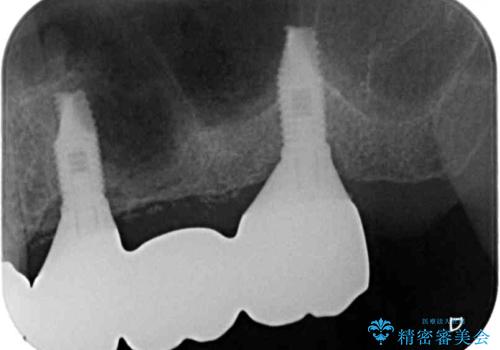

診査の結果、左側は奥歯2本、右側は1本の抜歯が必要であることが分かりました。

左側は大臼歯2本と小臼歯1本が欠損しているため、インプラント2本を治療したブリッジ、右側は中間欠損であり、前後の歯も加療が必要であったためブリッジによる補綴治療を行うこととしました。

抜歯となった歯は全て神経が抜かれた歯であり、強大な咬合力によって破折したことが原因で抜歯となりました。